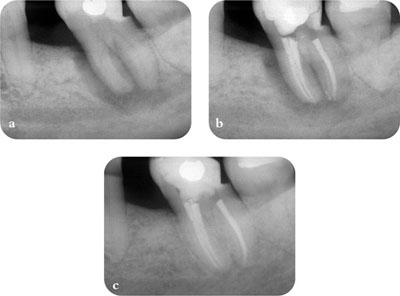

In essence, the task is to detect any features that are not consistent with the radiographic characteristics of healthy periapical tissues. If available, previous radiographs should be used for comparison to ascertain any differences in radiographic appearance with time (Fig 1-4).

Fig 1-4 Previous radiographs should be used for comparison when assessing treatment outcome. (a) Pre-op radiograph. (b) Post-op radiograph. (c) Two-year review radiograph.